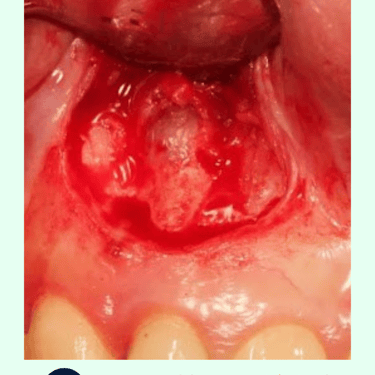

Incisión y Acceso: Se hace una incisión en la encía para acceder al hueso y al extremo de la raíz del diente.

Remoción de la punta de la raíz: Se corta el extremo de la raíz afectada y se eliminan el tejido infectado y cualquier quiste o absceso presente.